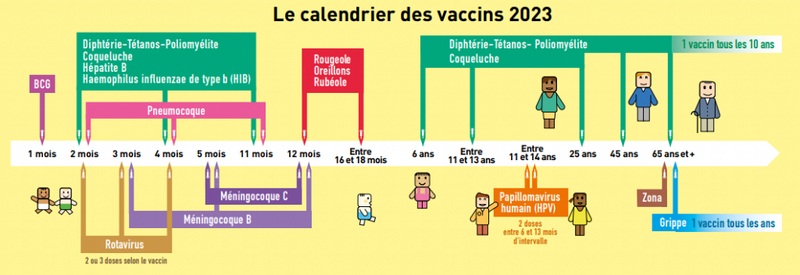

Calendrier Vaccinal 2023

Vous pourrez ici consulter quelles sont les recommandations vaccinales afin de savoir si vous-même ou vos enfants êtes à jour.